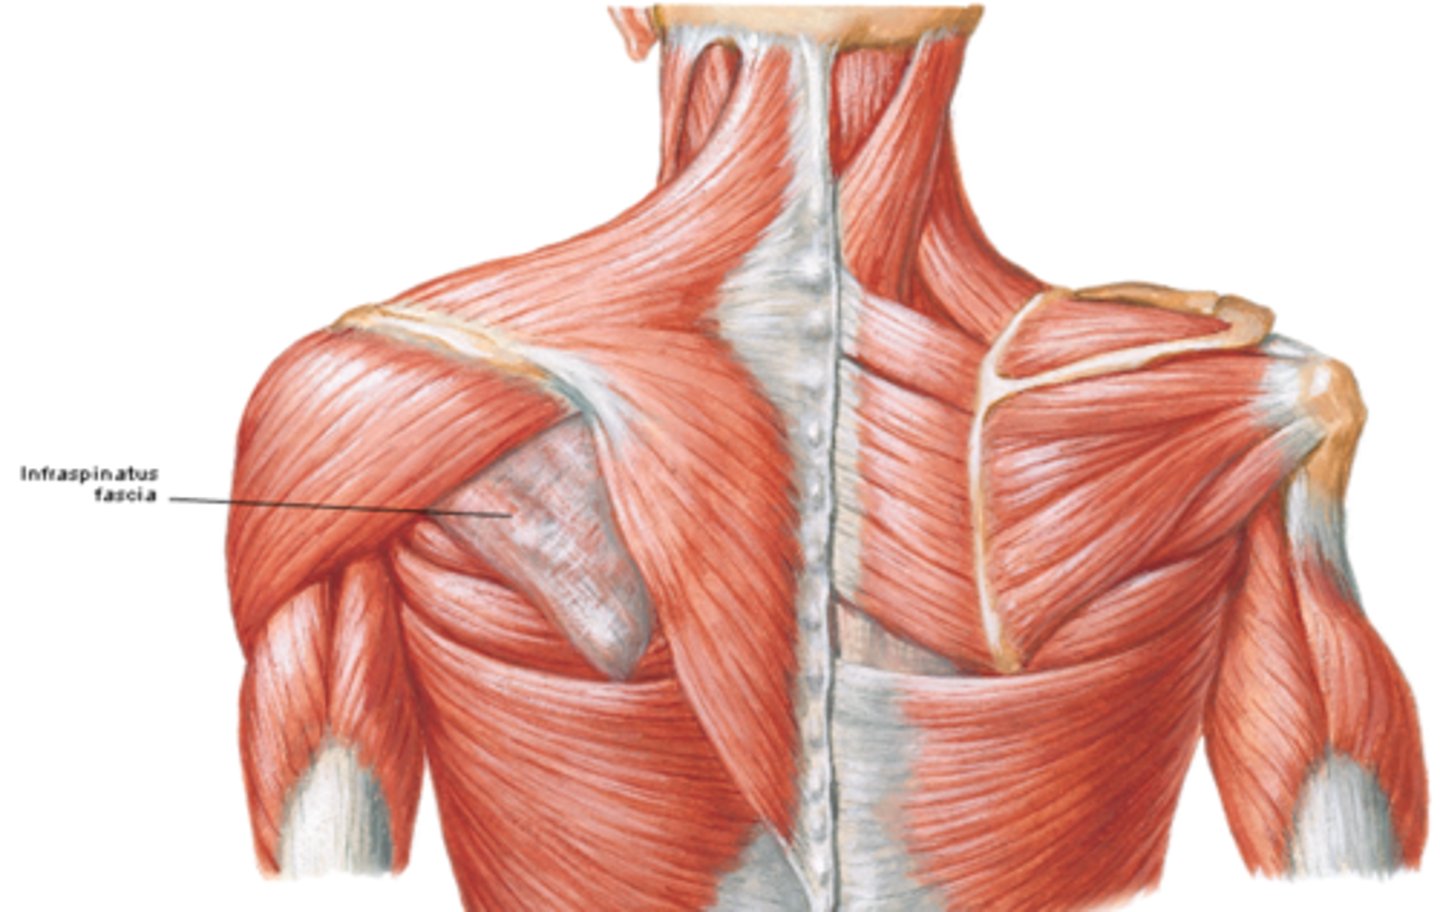

(Upper Limb Fascia:) Fascia of the shoulder region

•Deltoid fascia

•Supraspinous and infraspinous fascias

(Fascia of the shoulder region:) Deltoid fascia:

covers the deltoid muscle and is continuous anteriorly with the pectoral fascia and posteriorly with the infraspinous fascia

(Fascia of the shoulder region:) Supraspinous and infraspinous fascias:

overlies the supraspinatus and infraspinatus muscles, respectively; and attaches to the scapula